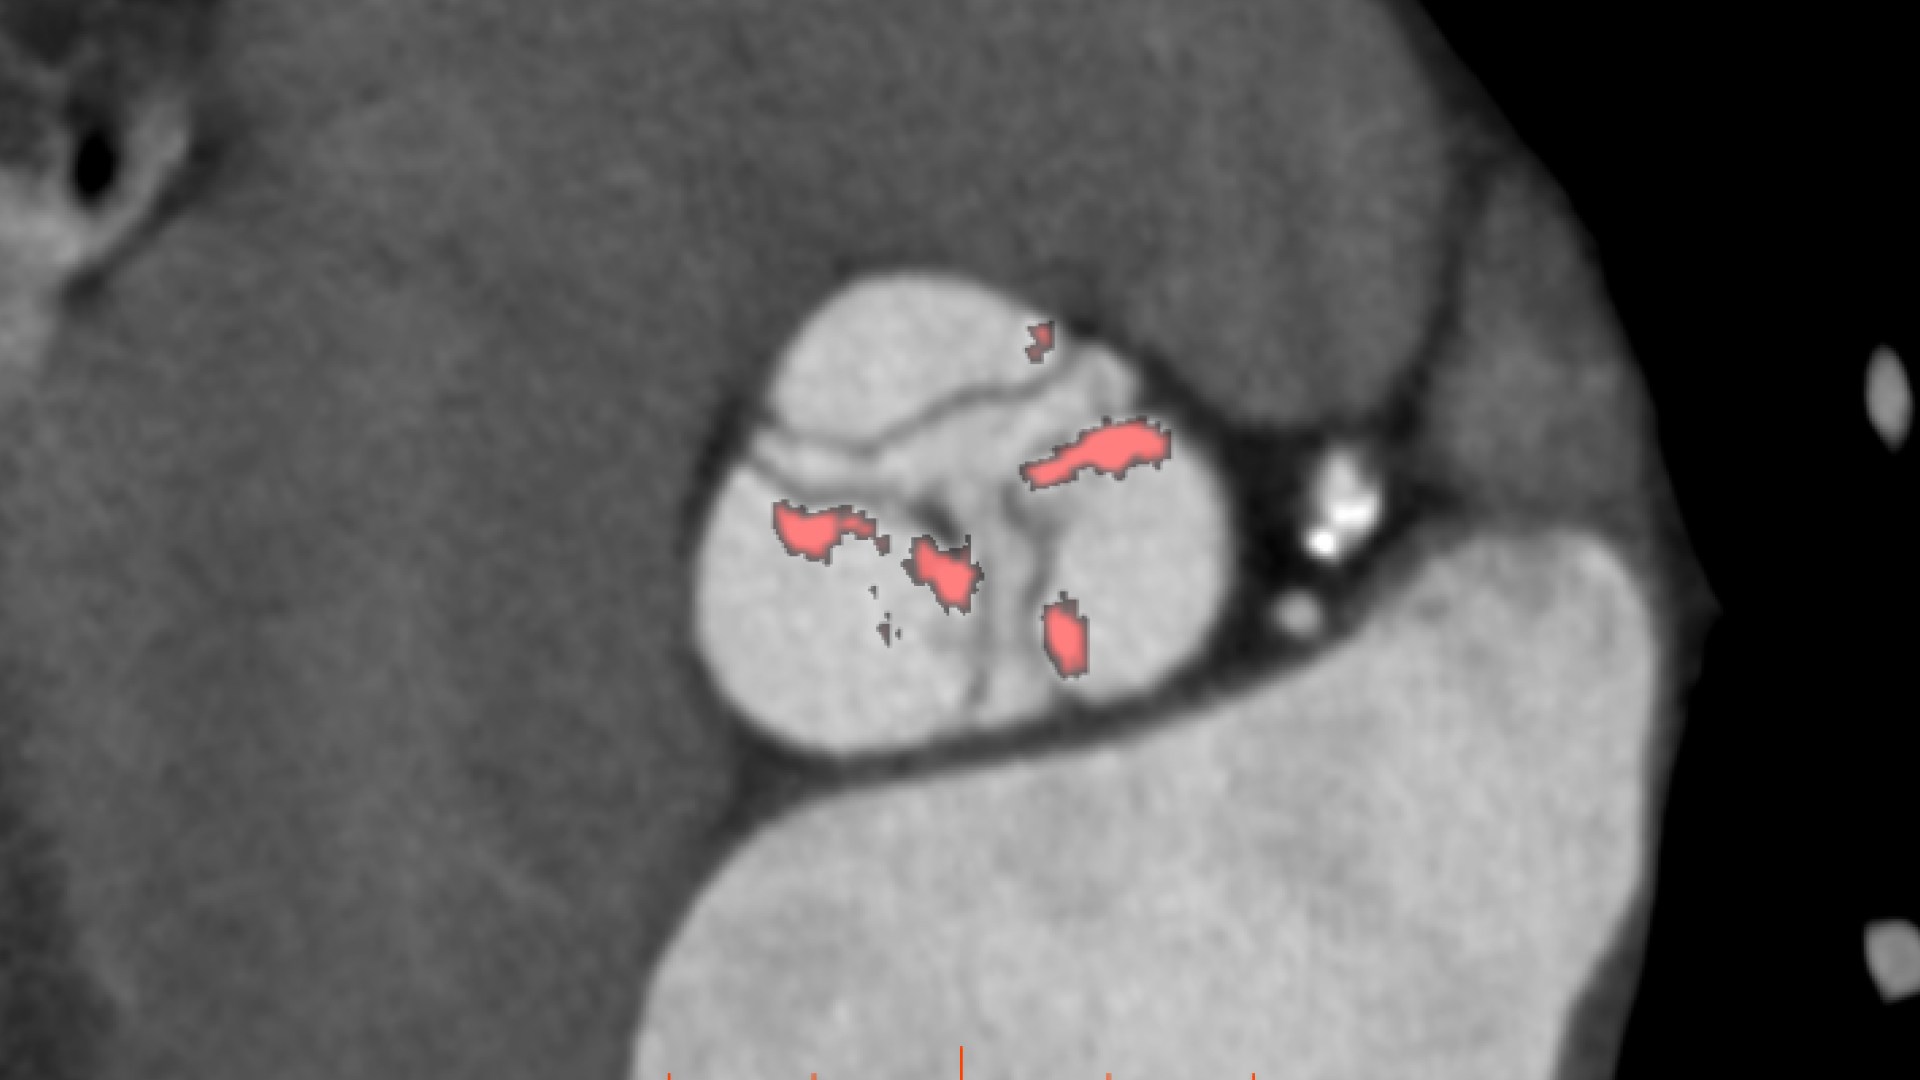

• Automatic estimate of aortic valve calcium volume measurement

• Automated aortic segmentation and preliminary orientation to aortic annular plane